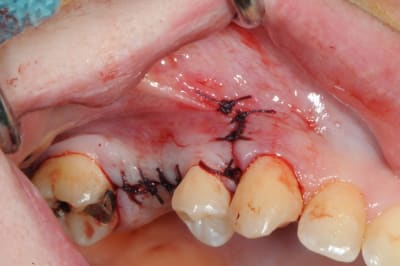

- mise en place de l'implant

- séchage discret de la surface osseuse

- injection du Vital Os en palatin et partout autour de l'implant

- hé hé hé ... pas de membrane de recouvrement, le matériaux se suffit à lui même. d'où une petite économie substantielle pour ceux qui ont l'habitude de mettre systématiquement une membrane après un Caldwell-Luc.

- sutures...